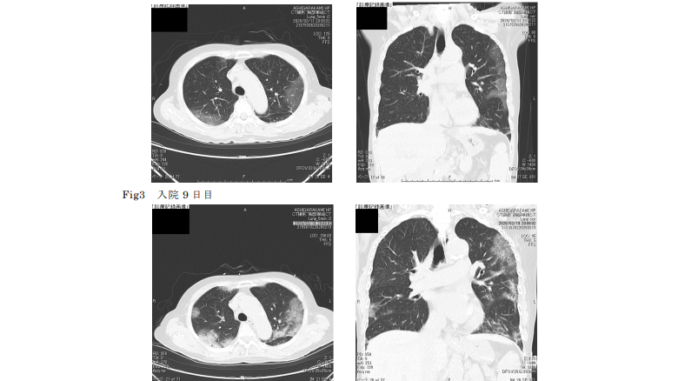

Con el consentimiento de los tres pacientes con neumonía se les aplicó ciclesonida, un tipo de tratamiento para el asma, en una etapa temprana y media de la infección.

Los tres pacientes, de más de 65 años, no estaban graves, pero todos mejoraron dos días después de recibir la ciclesonida el pasado 20 de febrero. Uno de ellos, una mujer de 73 años fue dada de alta, dijo el reporte.

Según explicaron, al llegar el medicamento inhalado a los pulmones, la inflamación de los pulmones se redujo en la zona donde se inhibe el virus. Las pruebas continúan. (International Press)